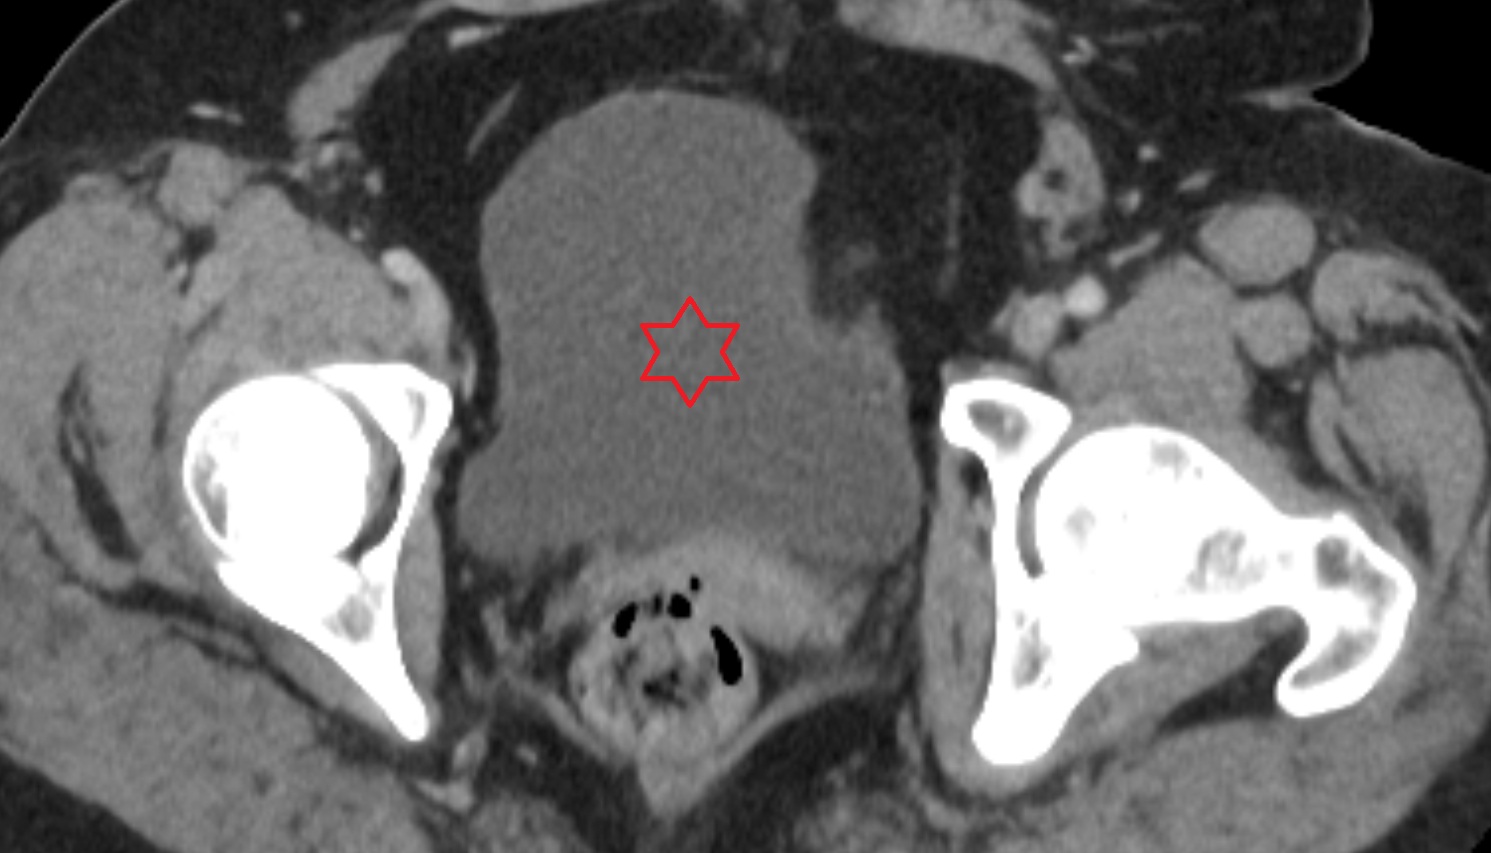

- Urinary bladder

- Uterus

- Ovaries

- Right ovary

- Left ovary